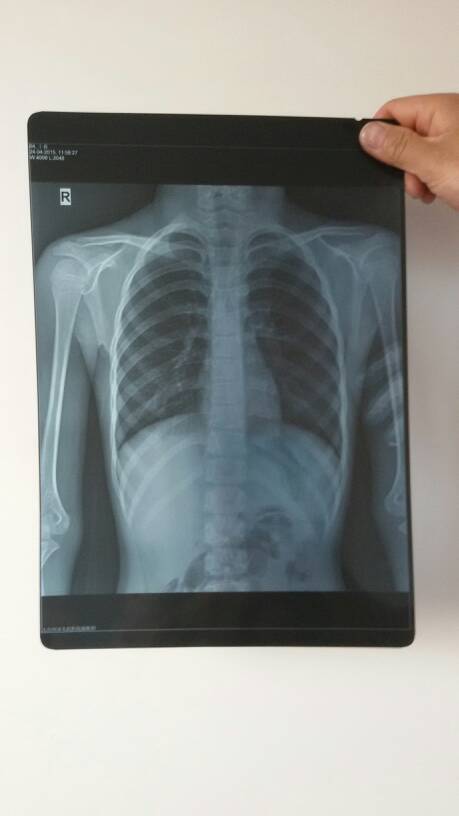

请懂医的亲,或者是好心的医生,帮忙看看这片子所显现的问题?到底是什么病,肺炎还是肺结核,孩子十虚岁!急急急急急急急!!!!!谢谢各位了!

建议你尽量带小孩上医院 如果单屏这张片看坐导卫出主要问题就是空动期 肺结核了 有时肺炎和肺结核的情况近似 会另人有些混淆呈勒 建近索议你到正规医生尽快治疗 以防感染其他器官

好象肺里有东西,快去大医院看看